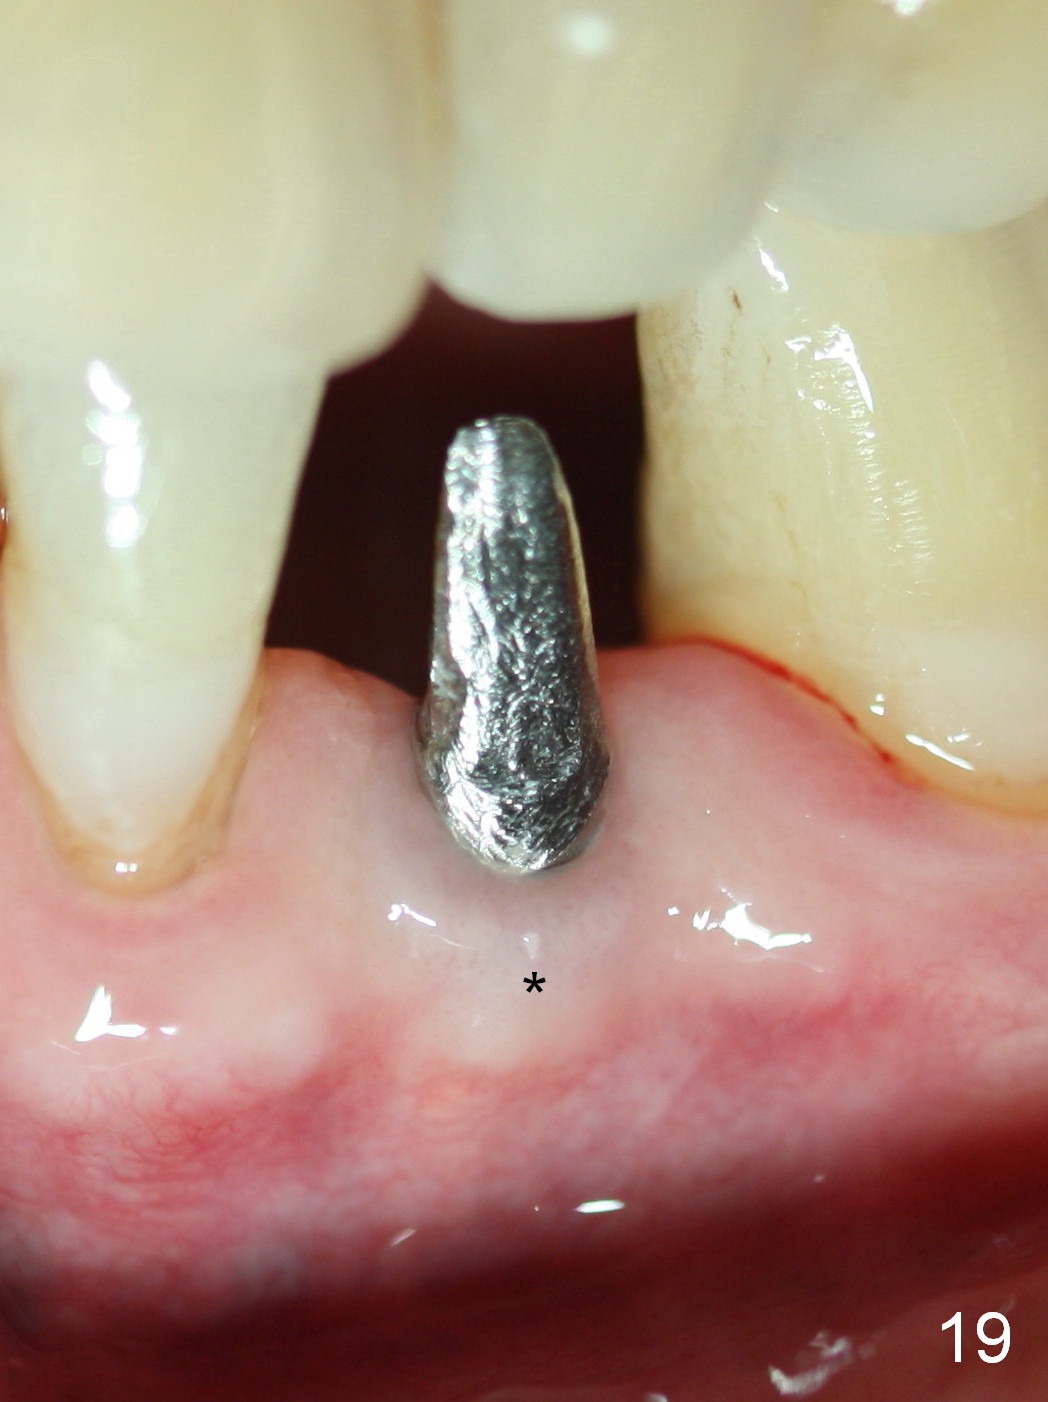

Five months postop, the peri-implant space reduces (Fig.18).  A keratinized band forms buccal to the implant (Fig.19 *).  The provisional dislodges probably due to the buccal placement (Fig.20).